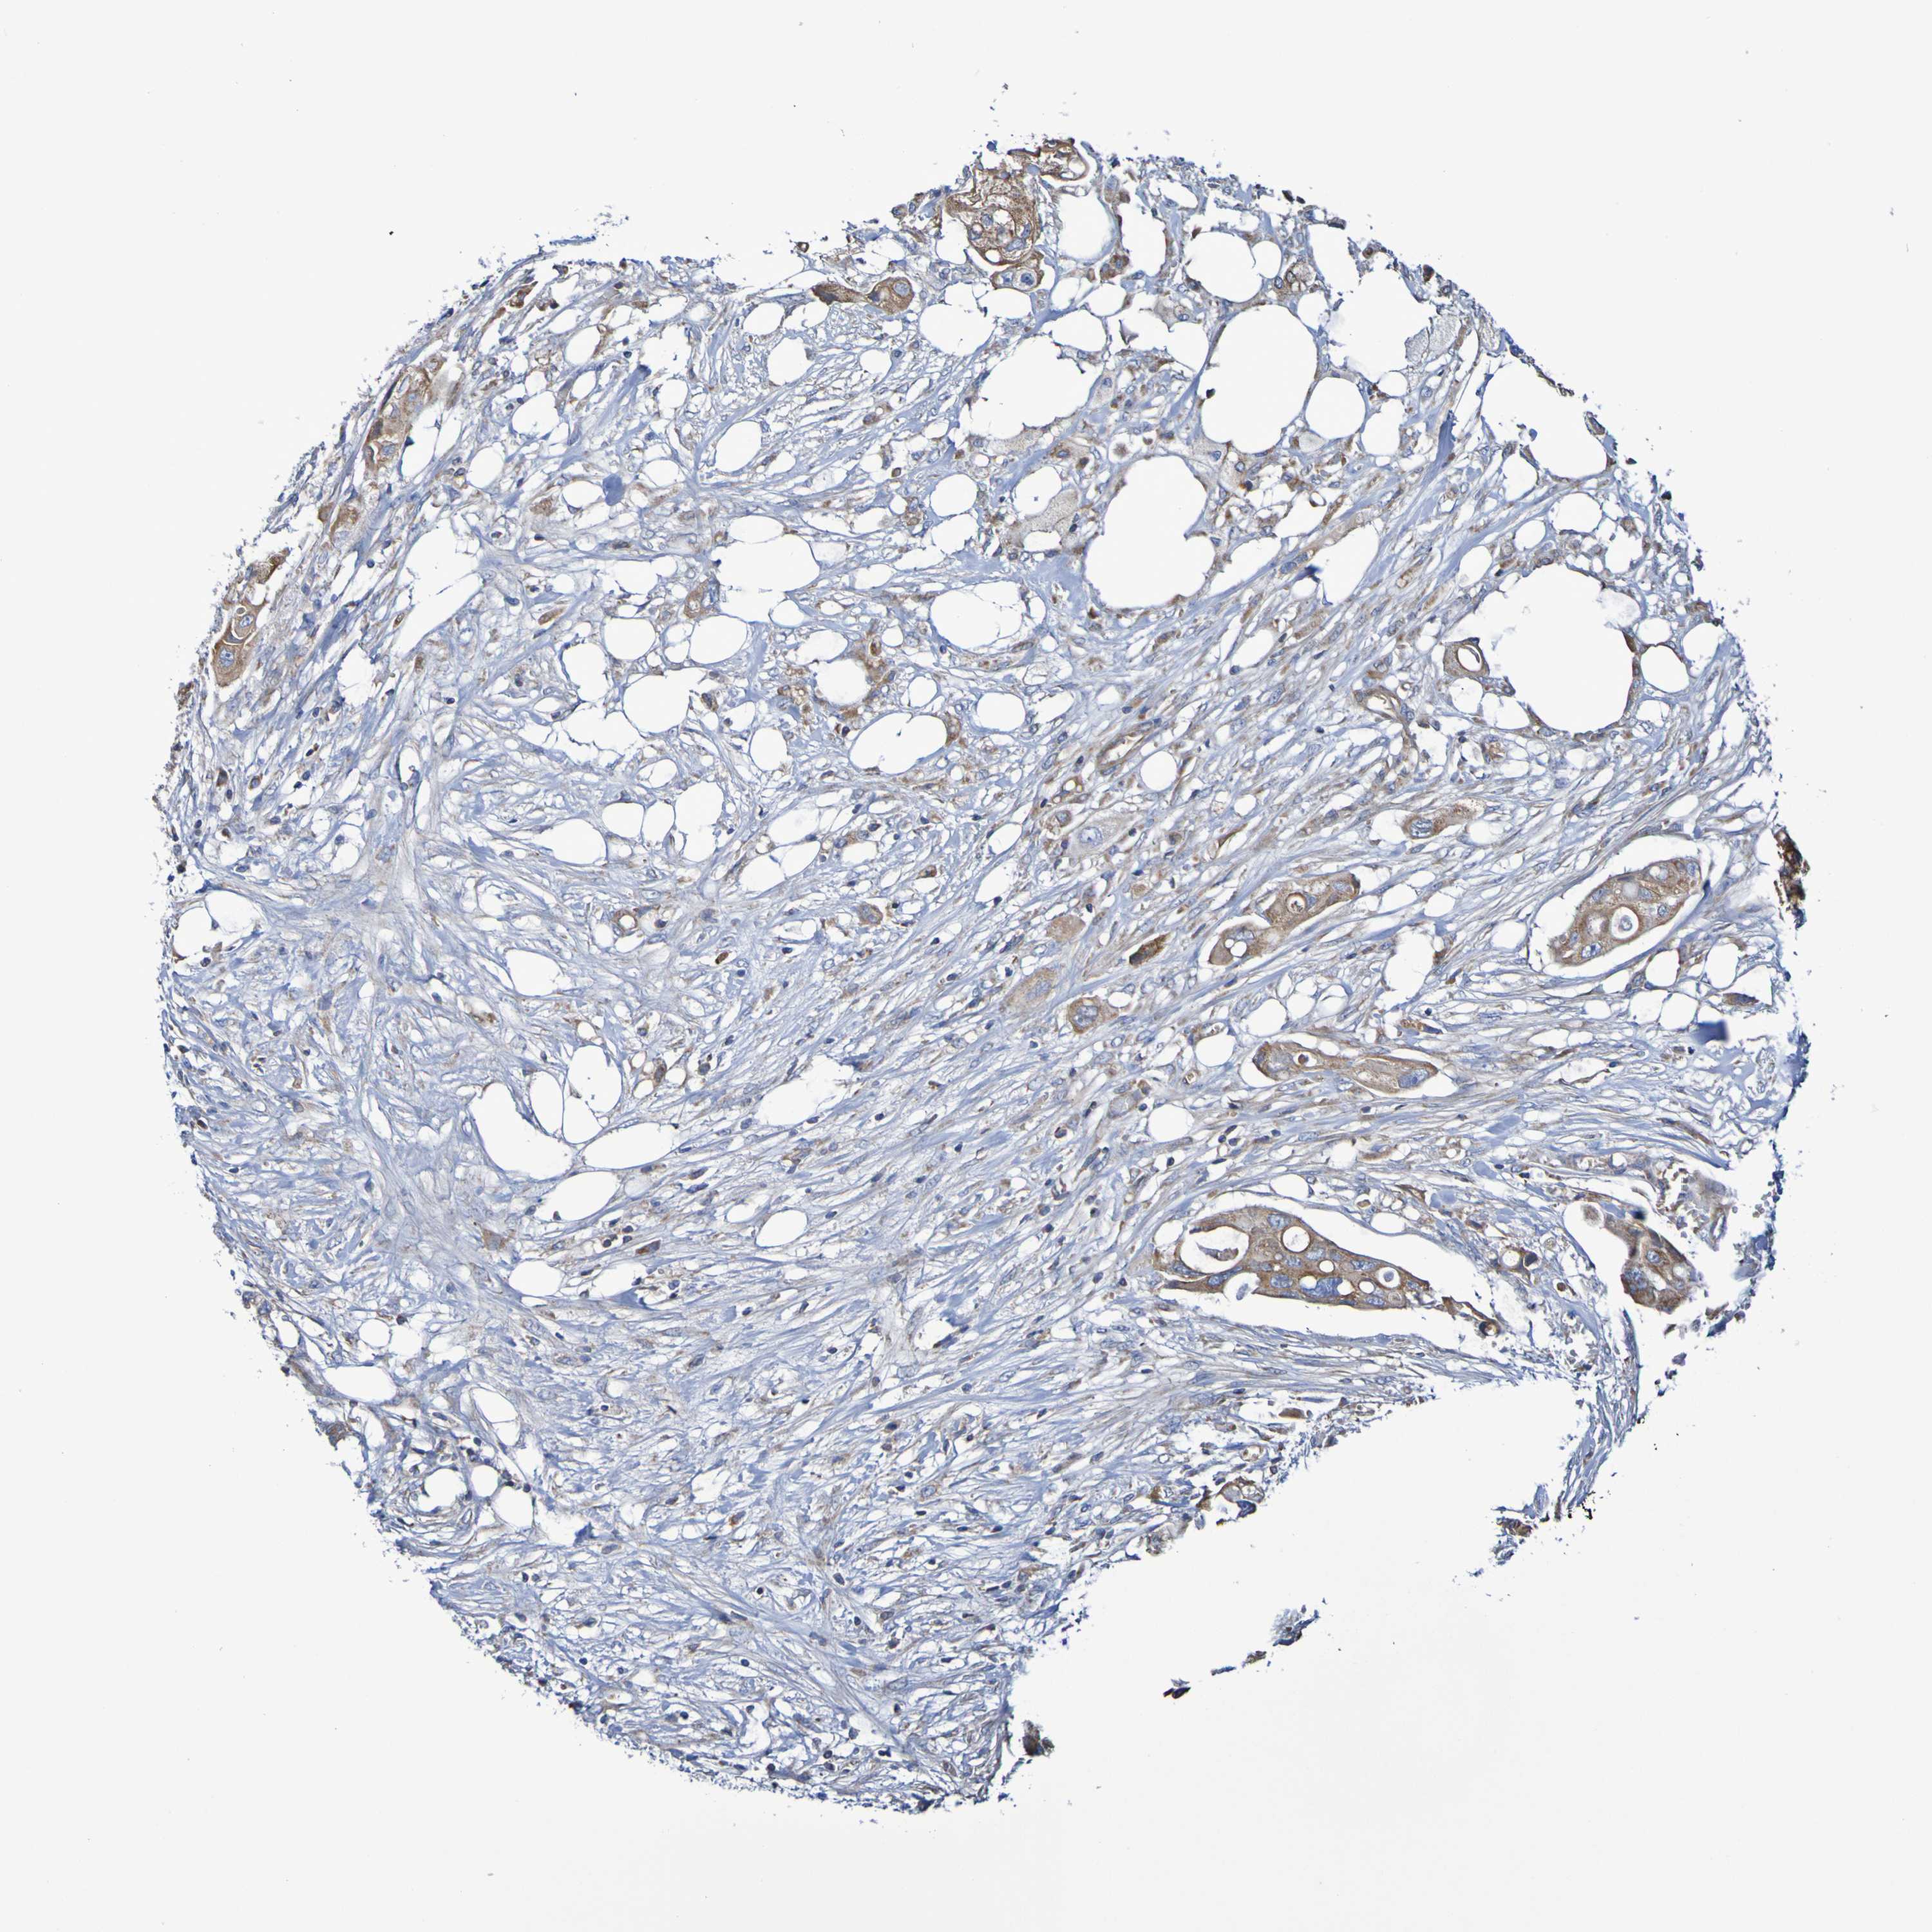

CANCER COLORECTAL CANCER Show tissue menu

Colorectal cancer

Rectum adenocarcinoma